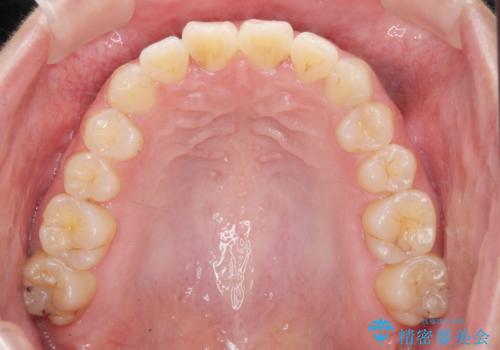

前歯のねじれをマウスピース矯正インビザラインで治療

- 長年気になっている、前歯のねじれの矯正治療を希望され来院されました。

十分にマウスピース矯正インビザラインで治療が可能と判断し、治療を進めることとしました。

長年気になっていた前歯のねじれが、ワイヤーをつけることなく矯正を行うことができ、大変喜んでいただくことができました。